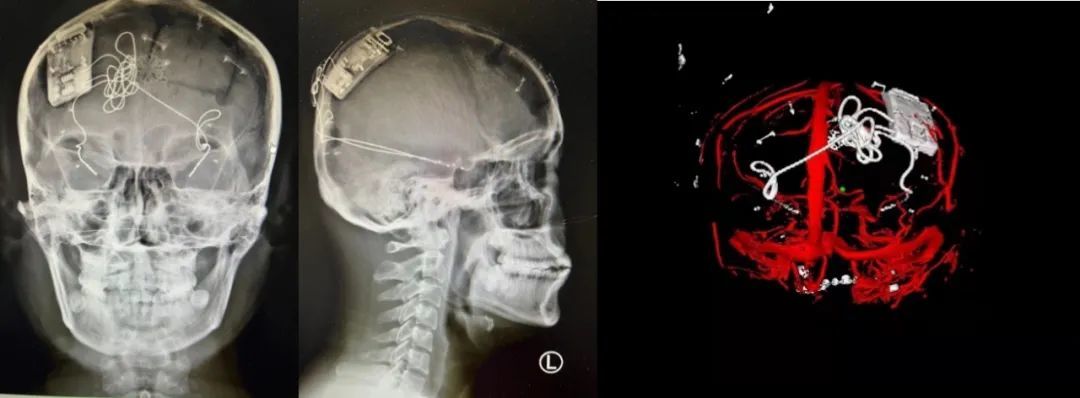

本次手術(shù)過(guò)程順利,術(shù)中刺激器各項(xiàng)指標(biāo)均工作正常,術(shù)后重建顯示電極位置精準(zhǔn),腦電信號(hào)清晰。患者為男性,入院后診斷為雙側(cè)顳葉癲癇,此類(lèi)癲癇為開(kāi)顱手術(shù)的相對(duì)禁忌癥,在藥物無(wú)法控制的情況下,傳統(tǒng)治療效果欠佳 。

術(shù)前經(jīng)過(guò)宣武醫(yī)院癲癇多學(xué)科專(zhuān)家團(tuán)隊(duì)詳細(xì)的臨床評(píng)估,包括視頻腦電監(jiān)測(cè)、頭顱磁共振及三維 CT 掃描、腦核醫(yī)學(xué)檢查等,全面評(píng)估了患者病情及致癇灶定位情況。

團(tuán)隊(duì)根據(jù)術(shù)前計(jì)劃,在手術(shù)機(jī)器人輔助下完成雙海馬長(zhǎng)軸電極及 IPG 植入,術(shù)后重建顯示電極位置精準(zhǔn),腦電信號(hào)清晰。術(shù)后第二天,患者即下床活動(dòng),身體狀況恢復(fù)良好。